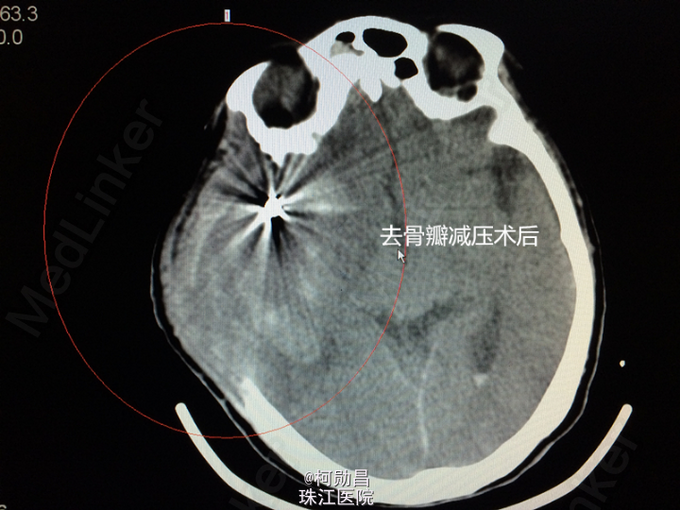

诊断:蛛网膜下腔出血破入脑室:动脉瘤? 处理:急诊予全脑血管造影提示:右侧大脑中动脉分叉处动脉瘤,予介入栓塞治疗(弹簧圈),并予去骨瓣减压术治疗。